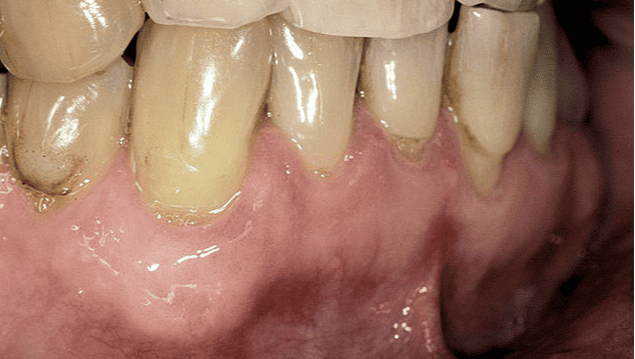

After